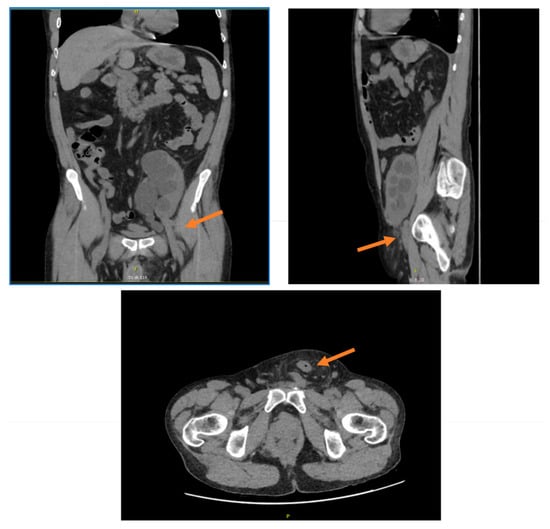

3.1. Case Report